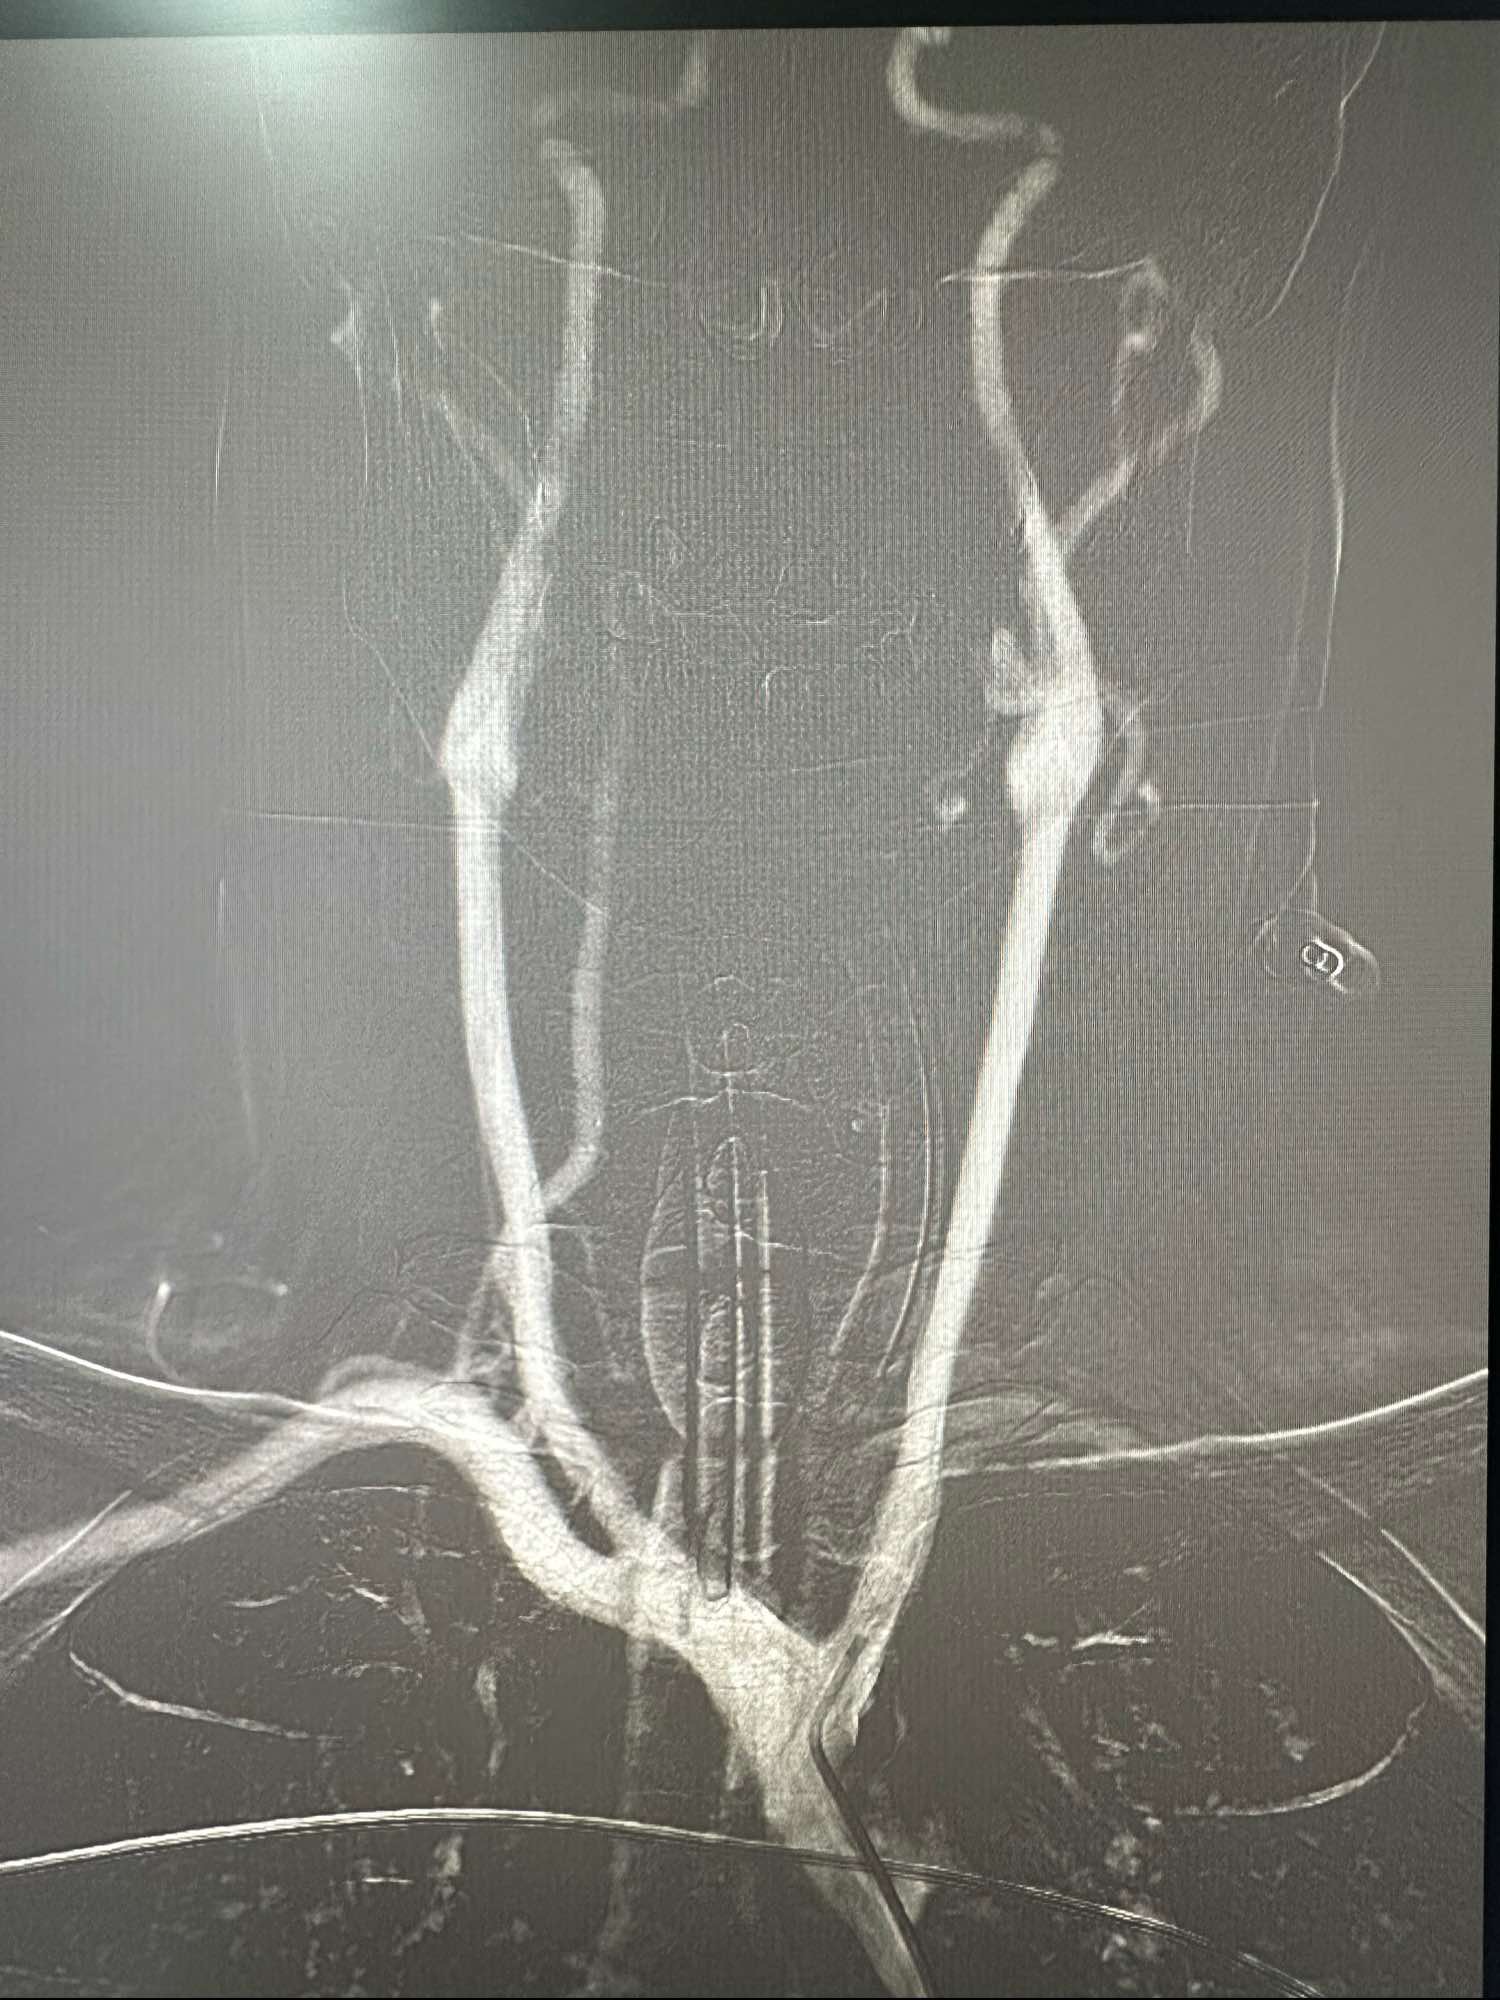

右侧颈内动脉造影正位

考虑牛角弓